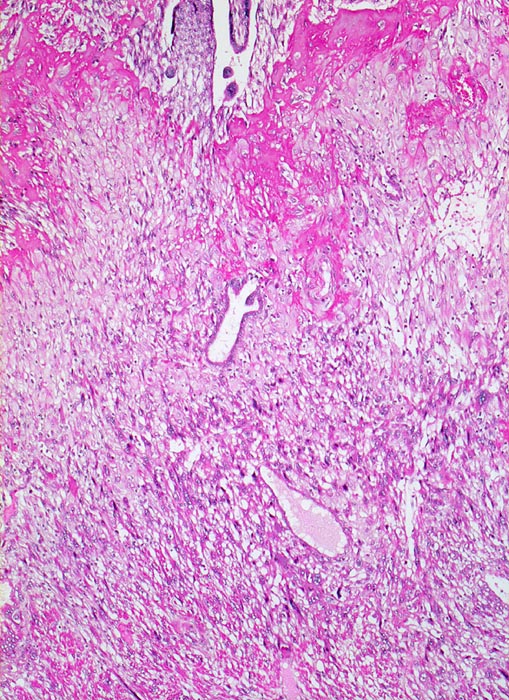

Morphologische Merkmale:

• Myometrium bedeckt von dezidualisiertem Endometriumstroma der Dezidua basalis.

• Invasion des Myometriums durch intermediären extravillösen Trophoblast.

• Fibrinoidschicht.

• Chorionzotten, ein Teil davon verankert mit dem dezidual transformierten Endometrium = Dezidua basalis (Haftzotten).

• Choriondeckplatte.

• Rechts oben Anteile des Chorion laeve.